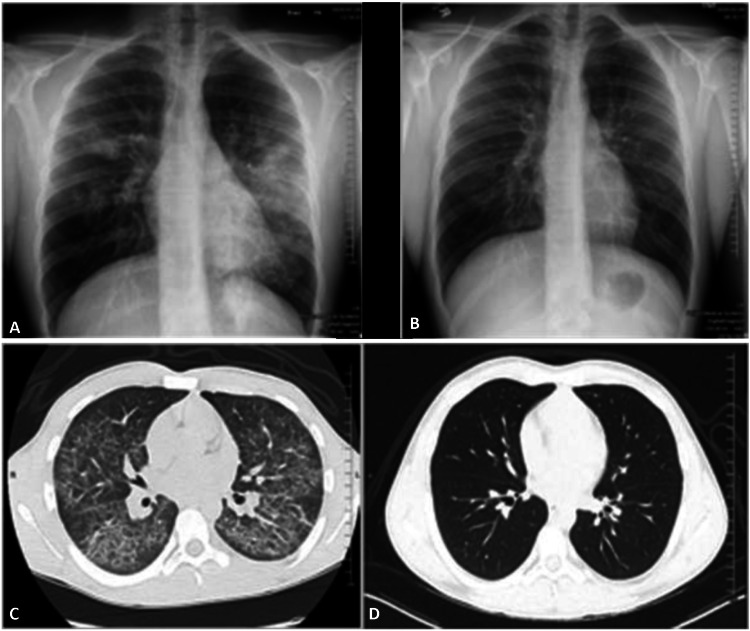

Chest radiographic findings were often bilateral, multifocal, and nonspecific. Two patients had a normal chest radiograph but showed abnormalities on chest computed tomography (CT). Chest computed tomography changes including multifocal, bilateral, and ground-glass opacities were noted in all patients, most severe in the dependent portions of the lung. Subpleural sparing was commonly described. Interstitial thickening was seen in almost all of the patients. Pneumomediastinum was seen in one patient. Lung consolidation was less frequent, usually occurring in more severe cases (Figures 1A–1D).

Routine chest radiographs were almost always performed, but were often nonspecific and could even be normal, and cannot be used as a reliable tool to evaluate EVALI. We found that the constellation of chest CT findings, which included bilateral ground-glass opacities (most commonly in the dependent portion of lungs), interstitial thickening, and peripheral sparing, was far more diagnostic and helped to exclude other differentials. Pneumomediastinum and consolidation were uncommon. Lab findings were also variable. The most consistent lab results were a significant leukocytosis and elevated inflammatory markers. We found trending inflammatory markers to be helpful in monitoring disease recovery as they correlated with symptoms.